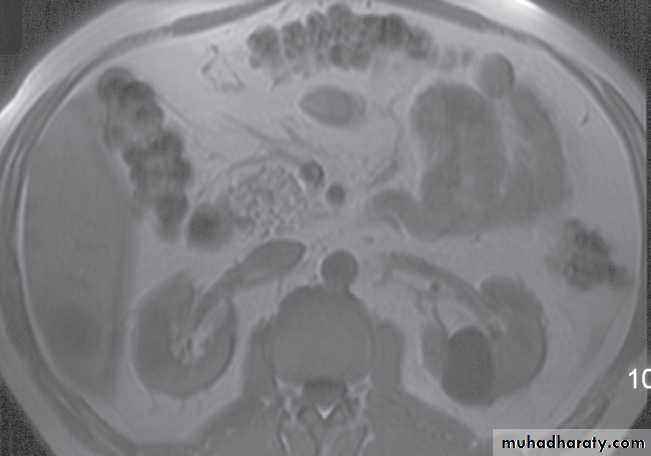

Normal magnetic resonance imaging

As with CT and ultrasound, the renal contours should be smooth. Corticomedullary differentiation is best seen on T1-weighted images and immediately following intravenous contrast enhancement with gadolinium .The renal collecting systems, ureters and bladder are best seen on T2-weighted images, as the fluid returns a high signal intensity .

Some normal variants are well demonstrated on MRI:

-Fetal lobulation & a column of Bertin (which is normal renal parenchyma that may look mass-like) .Special techniques